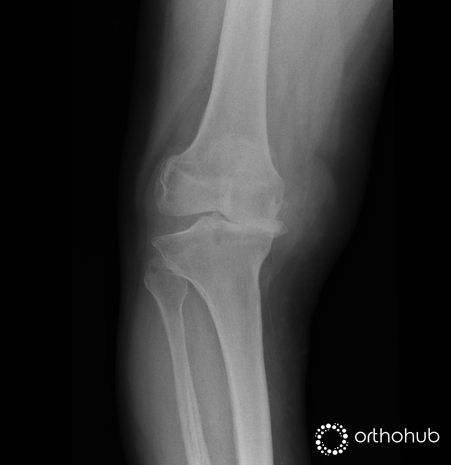

AP and Lateral radiographs

77 year old lady in severe pain in her knee. She had a previous open lateral meniscectomy at age 20, and a further open procedure for 'problems with her knee cap' 30 years ago.

On examination she has a clinical valgus deformity, and an elevated BMI.